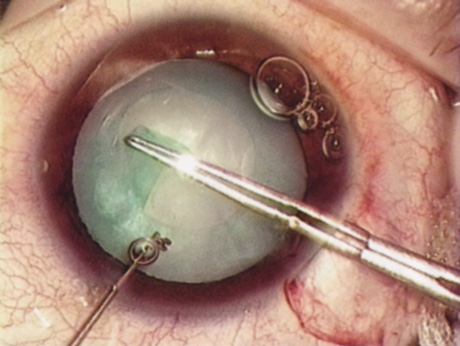

B-SCAN ULTRASOUND.

A mature cataract precludes visualization of the fundus. A B-scan ultrasonographic examination provides a real-time, two-dimensional (2D), cross-sectional image of the globe along the marked axis of the probe (Fig. 3). Cataracts are more common in patients with chronic retinal detachment, prior trauma, or intraocular tumors; therefore, a B-scan study is helpful in excluding structural posterior segment pathology before surgery on a mature cataract. Although a negative result to B-scan evaluation is reassuring, the surgeon should remember that it does not predict postoperative visual outcome. The B-scan can be thought of as a picture of Cincinnati from an airplane; the office buildings may all be standing, but you cannot tell whether the people in them are working.